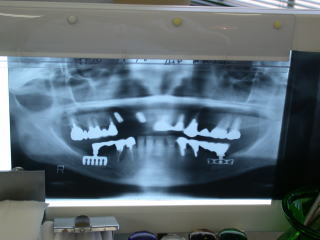

レントゲンを良く見ながら粘膜開窓し、ヒーリングアバットメントを装着します。

こちらの患者さんは下顎両側臼歯部にもインプラントを入れており、インプラントの良い点をご自身で感じています。